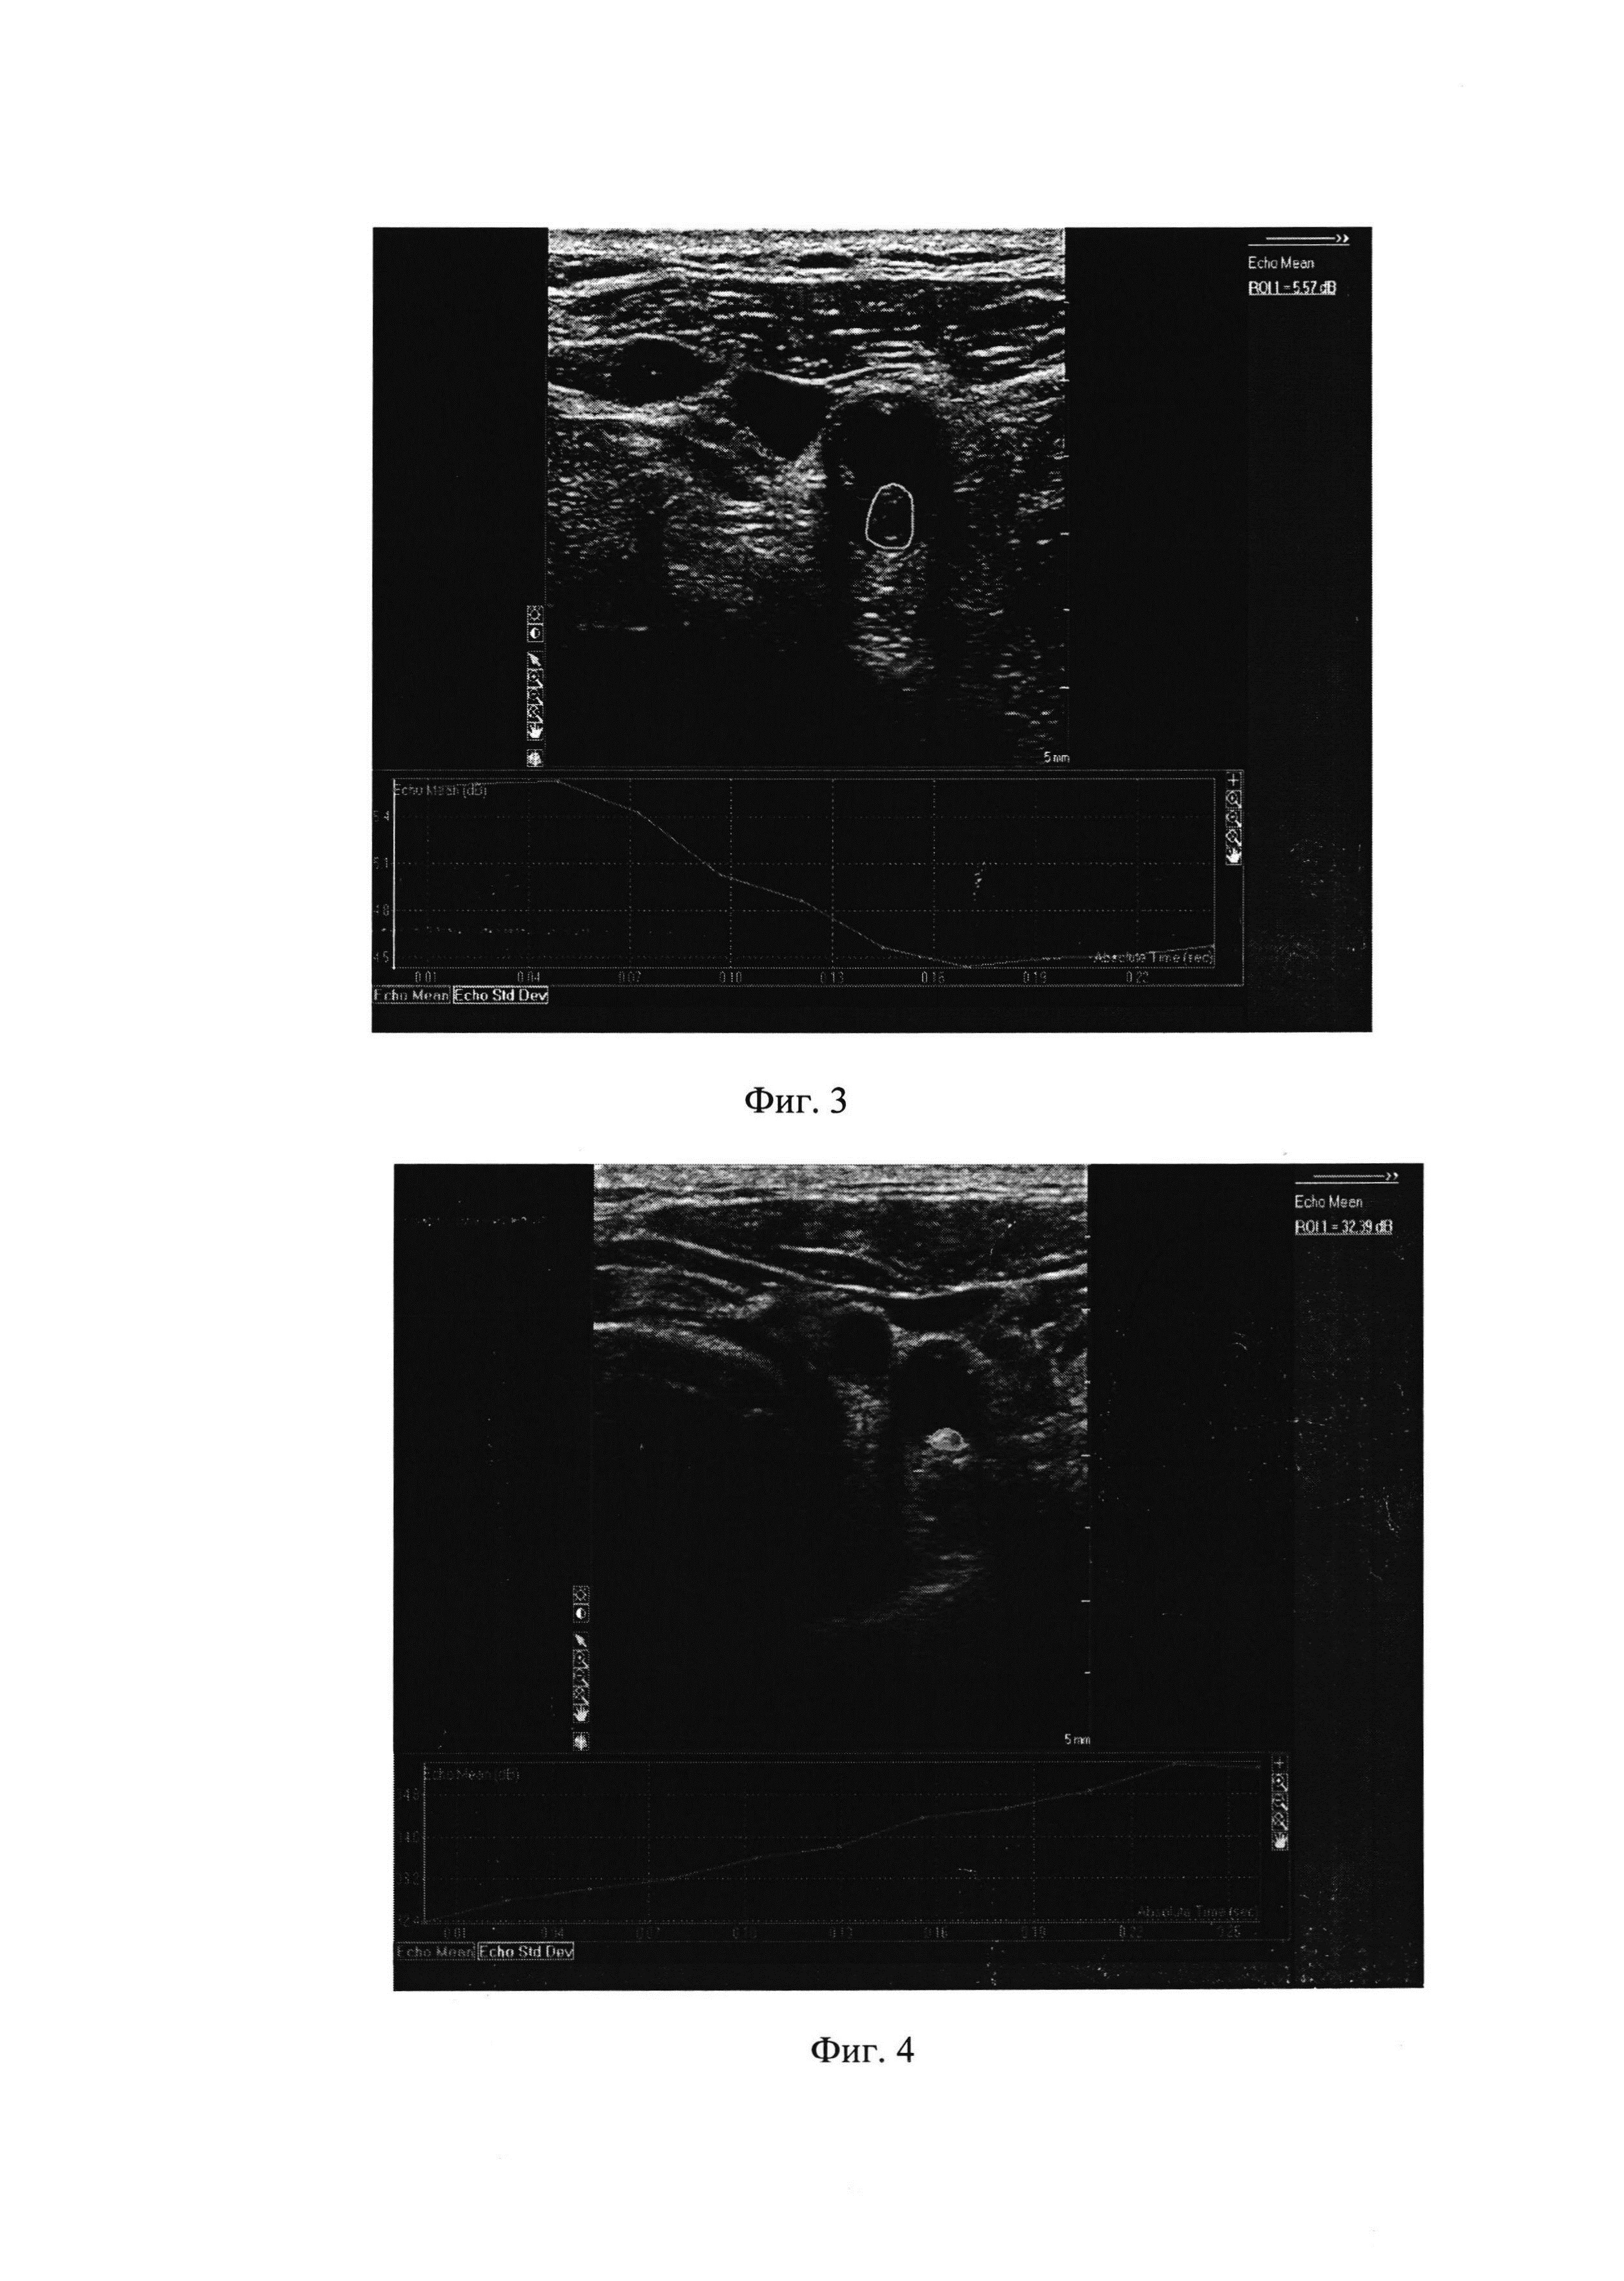

Изобретение относится к области медицины, в частности к неврологии, и может быть использовано при выборе оперативного вмешательства, в частности каротидной эндартерэктомии (КЭЭ) или ангиопластики со стентированием (КАС) при поражениях внутренних сонных артерий (ВСА) у больных с острыми эмболическими очагами ишемии в веществе головного мозга. Ангиореконструктивные операции на сонных артериях сопряжены с риском ишемического повреждения вещества головного мозга (как симптомного, так и асимптомного характера). Изучение послеоперационных асимптомных ишемических изменений в мозге, выявляемых при проведении МРТ, является предметом целого ряда исследований. В частности Ajay Gupta и соавт. в своем систематическом обзоре показали, что наличие асимптомного повреждения мозга по данным МРТ у пациентов без анамнестических сведений о наличии в анамнезе перенесенного инсульта было связано с двухкратным увеличением вероятности прогрессирования имеющейся когнитивной дисфункции и развитием инсульта в будущем [Ajay G., Ashley Е., Gino G et al. Silent Brain Infarction and Risk of Future Stroke. A systematic Review and Meta-Analysis. Stroke. 2016; 47: 719-725]. Кроме того эпидемиологические данные, полученные различными авторами, также свидетельствуют о том, что наличие асимптомного повреждения мозга может внести вклад в развитие когнитивной дисфункции, деменции, увеличения общей летальности и главного потенциального осложнения - инсульта [Bokura Н., Kobayashi S., Yamaguchi S. et al. Silent brain infarction and subcortical white matter lesions increase the risk of stroke and mortality: a prospective cohort study. J Stroke Cerebrovasc Dis. 2006; 15: 57-63]. Изучение механизмов формирования острых очагов ишемии является сложной задачей. Небольшой размер очагов ишемии, их локализация и хроническое ишемическое прекондиционирование мозга являются факторами, способными объяснить, почему некоторые цереброваскулярные события клинически не манифестируются [Fanning J.P., Wesley A.J., Wong A.A., Fraser J.F. Emerging spectra of silent brain infarction. Stroke. 2014; 45: 3461-3471]. Понимание того, в какой степени различные методы ангиовизуализации могут прогнозировать развитие повреждения вещества мозга, является чрезвычайно важным. В ряде исследований приводилась частота появления клинически асимптомных эмболических повреждений вещества мозга после процедуры стентирования (с использованием защитного устройства), которая сводилась к тому, что после КЭЭ острых очагов ишемии наблюдалось меньше, чем после стентирования. Schaudigel с соавт. в своем метаанализе показали, что среди 2117 пациентов (1363 пациентов группы КАС и 754 - группы КЭЭ) уровень острых очагов ишемии (ООИ) (по данным ДВ-МРТ) был существенно выше у пациентов группы КАС [Schnaudigel S., Groschel К., Pilgram S.M., Kastrup A. New brain lesion after carotid stenting versus carotid endarterectomy: a systematic review of the literature. Stroke. 2008; 39: 1911-1919]. В другом метаанализе, включающем данные 20 исследований, в которых проводилась сравнительная оценка повреждения мозга на основании ДВ-МРТ, показано, что частота эмболического повреждения головного мозга при КАС превышала таковую при КЭЭ [Gargiulo G., Sannino A., Stabile Е. et al. New cerebral lesion at magnetic resonance imaging after carotid artery stenting versus endarterectomy: an update meta-analysis. PloS One. 2015; 10 (5)]. Таким образом, методика выбора оперативного вмешательства при поражениях внутренних сонных артерий имеет важное значение в плане предотвращения послеоперационного эмболического повреждения головного мозга. На сегодняшний день известен способ выбора оперативного вмешательства при поражениях внутренних сонных артерий путем исследования пациента с помощью протокола CREST, включающего анамнестические симптоматические исследования и степень стеноза сонных артерий, при этом при наличии транзиторных ишемических атак, преходящей слепоты или малого инсульта до исследования сонной артерии в течение 180 дней до рандомизации, а также при наличии стеноза 50% и более при проведении ангиографии, или 70% и более при проведении КТ-ангиографии или магнитно-резонансной ангиографии, или 70% при ультразвуковом исследовании, которые имели место в течение предшествующих 6 месяцев или которые вызывали необходимость терапии антикоагулянтами, рекомендовалось проведение КАС и являлось противопоказанием к проведению КЭЭ [Brott T.G., Howard R.W., Howard G. et al. Stenting versus endarterectomy for treatment of carotid-artery stenosis. N Engl J Med., 2010; 363: 11-23.]. Однако данный способ не обладает высокой точностью при выборе оперативной тактики хирургического вмешательства для проведения КАС или КЭЭ у больных с поражением внутренних сонных артерий. Известен также способ выбора оперативного вмешательства при поражениях внутренних сонных артерий с использованием рандомизированных клинических исследований NASCET и ECST. Оценка степени выраженности морфологических изменений осуществлялась с помощью транскраниальной допплерографии, дуплексного сканирования артерий шеи, спиральной КТ-ангиографии/МР-ангиографии и церебральной ангиографии. А выбор оперативного вмешательства проводился по степени стеноза ВСА. Причем противопоказанием к проведению КЭЭ у «симптомных» больных являлись стеноз <30% без приема аспирина + хроническая окклюзия ВСА, а у «бессимптомных» больных - стеноз <60%; хроническая окклюзия ВСА; расслоение сонной артерии; стеноз >60% при уровне риска осложнений >6%. Противопоказанием к проведению каротидной ангиопластики со стентированием являлись асимптомные больные старше 80-ти лет; трудности доступа в артерию; тяжелый неврологический дефицит; выраженная атрофия мозга/лакунарные инфаркты; деменция. Из локальных факторов риска при стентировании следует отметить: выраженную концентрическую кальцификацию бляшки; тотальную окклюзию ВСА и выраженную деформацию дистального сегмента сонной артерии (Свистов Д.В. Хирургическое лечение атеросклеротических поражений артерий каротидного бассейна (диагностика, показания, противопоказания, перспектива). Санкт-Петербург, Международный неврологический журнал, 2005. - Т. 1, №1. - С. 59). Недостатками способа являются сложность его использования при выборе хирургического вмешательства при поражениях внутренних сонных артерий. Технический результат заключается в простоте исследования и расширении арсенала технических средств выбора оперативного вмешательства у больных с поражением внутренних сонных артерий с высокой при этом достоверностью и точностью. Технический результат достигается тем, что выбор оперативного вмешательства при поражениях внутренних сонных артерий проводят путем ультразвукового исследования атеросклеротических бляшек на поперечном срезе перед операцией линейным датчиком с частотой излучения 11 МГц в В-режиме с последующей регистрацией степени интенсивности акустического ультразвукового сигнала, отраженного от зон интереса - неоднородных компонентов, расположенных непосредственно под покрышкой атеросклеротической бляшки, и при наличии интенсивности акустических ультразвуковых сигналов от неоднородных компонентов бляшек сонной артерии 20 дБ и менее проводят оперативное вмешательство в виде каротидной эндартерэктомии, а при наличии интенсивности 28 дБ и более - в виде ангиопластики со стентированием. Способ осуществляется следующим образом. В предоперационном периоде проводят ультразвуковое исследование (для чего использовался прибор "iE 33" фирмы Philips). Ультразвуковое исследование атеросклеротических бляшек осуществляют на поперечном срезе перед операцией линейным датчиком с частотой излучения 11 МГц в В-режиме. После чего регистрируют степень интенсивности акустического ультразвукового сигнала, отраженного от зон интереса, а именно неоднородных компонентов, расположенных непосредственно под покрышкой исследуемой атеросклеротической бляшки. Неоднородность компонентов АСБ, расположенных под ее покрышкой, оценивают с помощью компьютерного анализа изображения и регистрации значений интенсивности акустических характеристик сигнала в зонах интереса с использованием программы ROI (Region of interest). Причем при наличии интенсивности акустических ультразвуковых сигналов от неоднородных компонентов бляшек сонной артерии, расположенных непосредственно под покрышкой АСБ, 20 дБ и менее проводят оперативное вмешательство в виде каротидной эндартерэктомии, а при наличии интенсивности 28 дБ и более - в виде ангиопластики со стентированием. Все включенные в исследование пациенты были распределены на 2 группы в зависимости от вида хирургического вмешательства. Первую группу составили 42 пациента, которым была выполнена КЭЭ из ВСА, вторую группу составили 36 больных, которым была проведена КАС (с использованием защитного устройства фильтрирующего типа). На основании анамнеза и результатов неврологического обследования выявлено, что в обеих исследуемых группах (как с КЭЭ, так и с КАС) чаще всего встречались пациенты с асимптомным течением заболевания (86% и 75%, соответственно). Основные характеристики обследованных пациентов в зависимости от вида хирургического вмешательства представлены в таблице 1. У подавляющего числа пациентов групп КЭЭ и КАС (95% и 94%, соответственно) диагностировалась артериальная гипертония, и каждый второй пациент имел два и более факторов риска развития сосудистого заболевания (см. таблица 1). Всем пациентам в предоперационном периоде проводилось ультразвуковое исследование (для чего использовался прибор "iE 33" фирмы Philips с линейным датчиком с частотой излучения 11 МГц). Степень неоднородности АСБ оценивалась с помощью компьютерного анализа изображения и регистрации значений интенсивности акустических характеристик сигнала в зонах интереса (неоднородных компонентов, расположенных непосредственно под покрышкой атеросклеротической бляшки) с использованием программы ROI (Region of interest). Во всех случаях через 24 часа после открытого хирургического либо эндоваскулярного вмешательства проводилось неврологическое обследование с учетом оценки дефицита по шкале инсульта NIH (J. Biller et. al., 1990, T. Brott et. al., 1989). Состояние вещества головного мозга до и через 24 часа после хирургического и эндоваскулярного лечения оценивали по результатам ДВ-МРТ (Magnetom Verio, Siemens, 3 Тесла). Ввиду преобладания очагов малых размеров оценка поражения вещества головного мозга проводилась на диффузионно-взвешенных изображениях с коэффициентом диффузионного взвешивания b=1000. Для интенсивности ультразвукового сигнала различие средних величин (в разных группах) оценивали (проверив близость распределений к нормальному) критерием Стьюдента, а пороговые величины определили ROC-анализом. Сбалансированность сравниваемых (по интенсивности ультразвукового сигнала) групп по характеристикам, значимо прогностически неблагоприятным (по информации из литературы) для образования острых очагов ишемии, проверили однофакторным анализом. Результаты считали статистически значимыми при р≤0,05. Для расчетов использовали статистический пакет SAS 9.3 (SAS Institute, Inc, Cary, NC). Результаты исследования У всех пациентов процедуры по ангиореконструкции были осуществлены успешно, клинических проявлений развития острого НМК в послеоперационном периоде ни у кого не наблюдалось. Однако при нейровизуализационном ДВ-МРТ исследовании через 24 часа после операции у 25 (32%) пациентов при отсутствии отрицательной неврологической динамики наблюдались появления острых очагов ишемии (ООИ). Анализ данных ДВ-МРТ головного мозга показал, что после КЭЭ очаги ишемии на стороне вмешательства имеются у 9 (21%) пациентов, причем ООИ сразу в обоих полушариях большого мозга наблюдались только в одном случае. У пациентов группы КАС очаги ишемии были выявлены в 16 (43%) случаях, в 7 случаях они располагались билатерально. Таким образом, при проведении операций на ВСА развитие ООИ в веществе головного мозга (включая случаи локализации очагов в обоих полушариях) статистически значимо чаще (р=0,05) наблюдалось у пациентов после КАС по сравнению с КЭЭ. Сопоставление анамнеза и результатов неврологического обследования пациентов двух групп с выявленными изменениями на ДВ-МРТ представлены в таблице 2. Анализ изменений вещества мозга после проведенных вмешательств показал, что у большинства (78%) клинически симптомных больных после стентирования обнаруживается повышенная тенденция к образованию ООИ. Различия в количестве очагов ишемии у клинически асимптомных и симптомных больных, подвергшихся операции КЭЭ, не наблюдалось (см. таблица 2). У пациентов группы КЭЭ новые очаги ишемического повреждения вещества мозга наблюдались в 9 (21%) случаях, причем у всех у них интенсивность ультразвукового сигнала (при предоперационном исследовании) была от 28 дБ и выше. У пациентов без послеоперационного повреждения вещества мозга 33 (79%) отмечался сдвиг интенсивности ультразвукового сигнала (при предоперационном исследовании) в сторону более низких показателей (менее 28 дБ). Это различие значений интенсивности ультразвукового сигнала также было статистически значимым (р=0,05). Согласно нашим данным у пациентов группы КАС с послеоперационными верифицированными новыми очагами ишемии в веществе мозга ультразвуковой сигнал при дооперационном обследовании был низкоинтенсивным и составлял от 20 дБ и ниже, при отсутствии послеоперационных очагов ишемии ультразвуковой сигнал при дооперационном обследовании был статистически значимым (р=0,01) другим, высокоинтенсивным, и достигал более 20 дБ (см. таблица 3). Возникновение послеоперационных очагов ишемии оказалось связано с интенсивностью ультразвукового сигнала (измеренного при дооперационном обследовании), причем характер этой связи в группах КЭЭ и КАС оказался различный: в группе КЭЭ послеоперационные очаги ишемии ассоциировались с высокоинтенсивными ультразвуковыми сигналами, а в группе КАС, наоборот, с низкоинтенсивными (см. фиг. 1). На фиг. 1 представлена интенсивность ультразвукового сигнала, отраженного от каротидной бляшки (при предоперационном ультразвуковом обследовании), у пациентов с послеоперационно выявленными очагами ошемии (•) и без них (о) в группах, перенесших каротидную ангиопластику со стентированием (КАС) и каротидную эндартерэктомию (КЭЭ). На чертеже видно, что при КАС эмбологенными были бляшки, имевшие преимущественно низкоинтенсивные предоперационные ультразвуковые сигналы (менее 20 дБ), а при КЭЭ - высокоинтенсивные (более 28 дБ). Низко- и высокоинтенсивные ультразвуковые сигналы, разделяемые точками отсечения (порогами классификации), различались (по медиане) статистически значимо (р=0,05): 10,1 против 36,9 (для группы КЭЭ) и 16,1 против 26,4 (для группы КАС). Точка отсечения низко- и высокоинтенсивных ультразвуковых сигналов (ассоциированных с наличием или отсутствием послеоперационных очагов ишемии) для группы КЭЭ определена визуально (поскольку подгруппы низко- и высокоинтенсивных сигналов в этой группе не пересекаются) и равна 28 дБ, точка отсечения для группы КАС определена с применением ROC-анализа (см. фиг. 2) (поскольку низко- и высокоинтенсивные сигналы в этой группе частично пересекаются) и равна 20 дБ (AUC = 87%, р = 0,05). На фиг. 2 представлена характеристическая (ROC) кривая информативности предоперационного ультразвукового метода прогнозирования эмболических повреждений головного мозга при каротидной ангиопластике со стентированием: чувствительность метода равна 75%, специфичность − 100% (при точке отсечения низко- и высокинтенсивных ультразвуковых сигналов равной 20 дБ). Следовательно, для случая КЭЭ чувствительность и специфичность предоперационного ультразвукового метода прогнозирования послеоперационных эмболических повреждений головного мозга равны и составляют 100% (при точке отсечения низко- и высокоинтенсивных сигналов равной 28 дБ), а для случая КАС чувствительность метода составляет 75%, а специфичность − 100% (при точке отсечения 20 дБ). Примеры осуществления способа Пример 1 Пациент С., 58 лет. Клинический диагноз: Дисциркуляторная энцефалопатия, стадия декомпенсации. Артериальная гипертония 3 ст., 2 ст. Атеросклероз. Стеноз правой внутренней сонной артерии 75-80%. Хронический бронхит курильщика. Хронический гастрит, ремиссия. Жалобы при поступлении в ФГБНУ «Научный центр неврологии» на снижение памяти и концентрации внимания в течение последних двух недель. Из анамнеза заболевания известно, что длительное время страдает артериальной гипертонией с повышением цифр артериального давления до 170/100 мм ртутного столба. Регулярно антигипертензивные препараты не принимал, артериальное давление не контролировал. В неврологическом статусе при поступлении определялась интенция при выполнении координаторных проб, пошатывание в позе Ромберга. При проведении дуплексного сканирования магистральных артерий головы выявлен атеросклеротический стеноз правой внутренней сонной артерии 75-80% за счет неоднородной по структуре с преобладанием гипоэхогенного компонента атеросклеротической бляшки. При проведении ультразвукового исследования с последующим определением степени интенсивности ультразвукового сигнала отраженного от зон, располагающихся под покрышкой атеросклеротической бляшки получено значение, составляющее 5,57 дБ (см. фиг. 3). По данным МРТ головного мозга до операции – изменения в обоих полушариях большого мозга сосудистого генеза. Наличие атеросклеротического стеноза правой внутренней сонной артерии 75-80%, с целью первичной профилактики развития нарушения мозгового кровообращения, принято решение о проведении каротидной эндартерэктомии из правой внутренней сонной артерии. Появления острой очаговой неврологической симптоматики после вмешательства не зафиксировано. При проведении ДВ-МРТ головного мозга через 24 часа после вмешательства очагов повышенной интенсивности МР-сигнала в веществе головного мозга не выявлено. Пример 2 Пациент П., 74 лет. Клинический диагноз: Атеросклероз. Стеноз левой внутренней сонной артерии 80-85%. Артериальная гипертония 1 ст. Хронический бронхит курильщика. При поступлении в ФГБНУ «Научный центр неврологии» пациент предъявлял жалобы на нестабильность цифр артериального давления с максимальным повышением до 190/100 мм ртутного столба. При проведении дуплексного сканирования выявлен стеноз левой внутренней сонной артерии 80-85%. Пациент консультирован ангиохирургом, рекомендовано хирургическое лечение. В неврологическом статусе при поступлении очаговой неврологической симптоматики не определялось. При проведении дуплексного сканирования магистральных артерий головы подтвержден атеросклеротический стеноз левой внутренней сонной артерии 80-85% за счет неоднородной по структуре с преобладанием гиперэхогенного компонента атеросклеротической бляшки. При проведении ультразвукового исследования с последующим определением степени интенсивности ультразвукового сигнала отраженного от зон, располагающихся под покрышкой атеросклеротической бляшки получено значение, составляющее 32,39 дБ (см. фиг. 4). По данным МРТ головного мозга до операции выявлены сосудистые очаги в обоих полушариях большого мозга. Наличие атеросклеротического стеноза левой внутренней сонной артерии 80-85%, с целью первичной профилактики развития нарушения мозгового кровообращения, принято решение о проведении каротидной ангиопластики со стентированием левой внутренней сонной артерии. Появления острой очаговой неврологической симптоматики после вмешательства не зафиксировано. При проведении ДВ-МРТ головного мозга через 24 часа после вмешательства изменений в веществе головного мозга не выявлено. Таким образом, заявленный способ обладает высокой достоверностью и точностью выбора оперативного вмешательства при поражениях внутренних сонных артерий и кроме того он прост в использовании и доступен практически в любом лечебном учреждении.